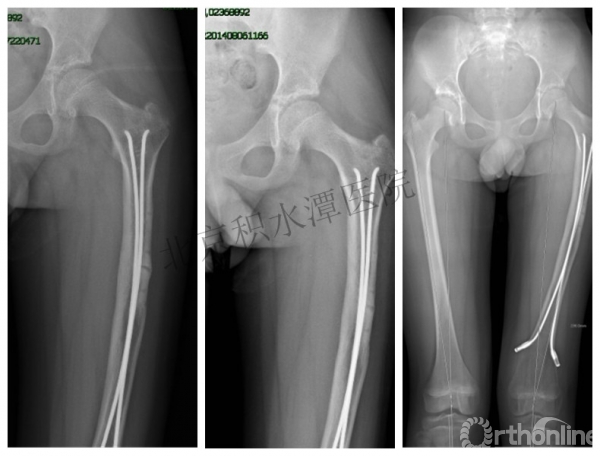

男孩 、5岁,初次骨折于2007年7月。

术后2年→再骨折→再次手术

钢板固定后一年

取板后再骨折→TEN

TEN取出后2个月

闭合复位再固定加尾帽

又过了4年!时间来到2015年

一年以后顺利愈合,实则危机四伏

数月后再骨折!牵引!

髋人字支具

外固定架术后一年

整整11年!是否治疗终结?

病人的付出?医生当反思!

一、思考

1.使用了医生可以使用的所有固定方式

2.似乎哪一次的处理都没有违背原则

3.问题出在哪儿?

4.骨折治疗—手术不是万能的!